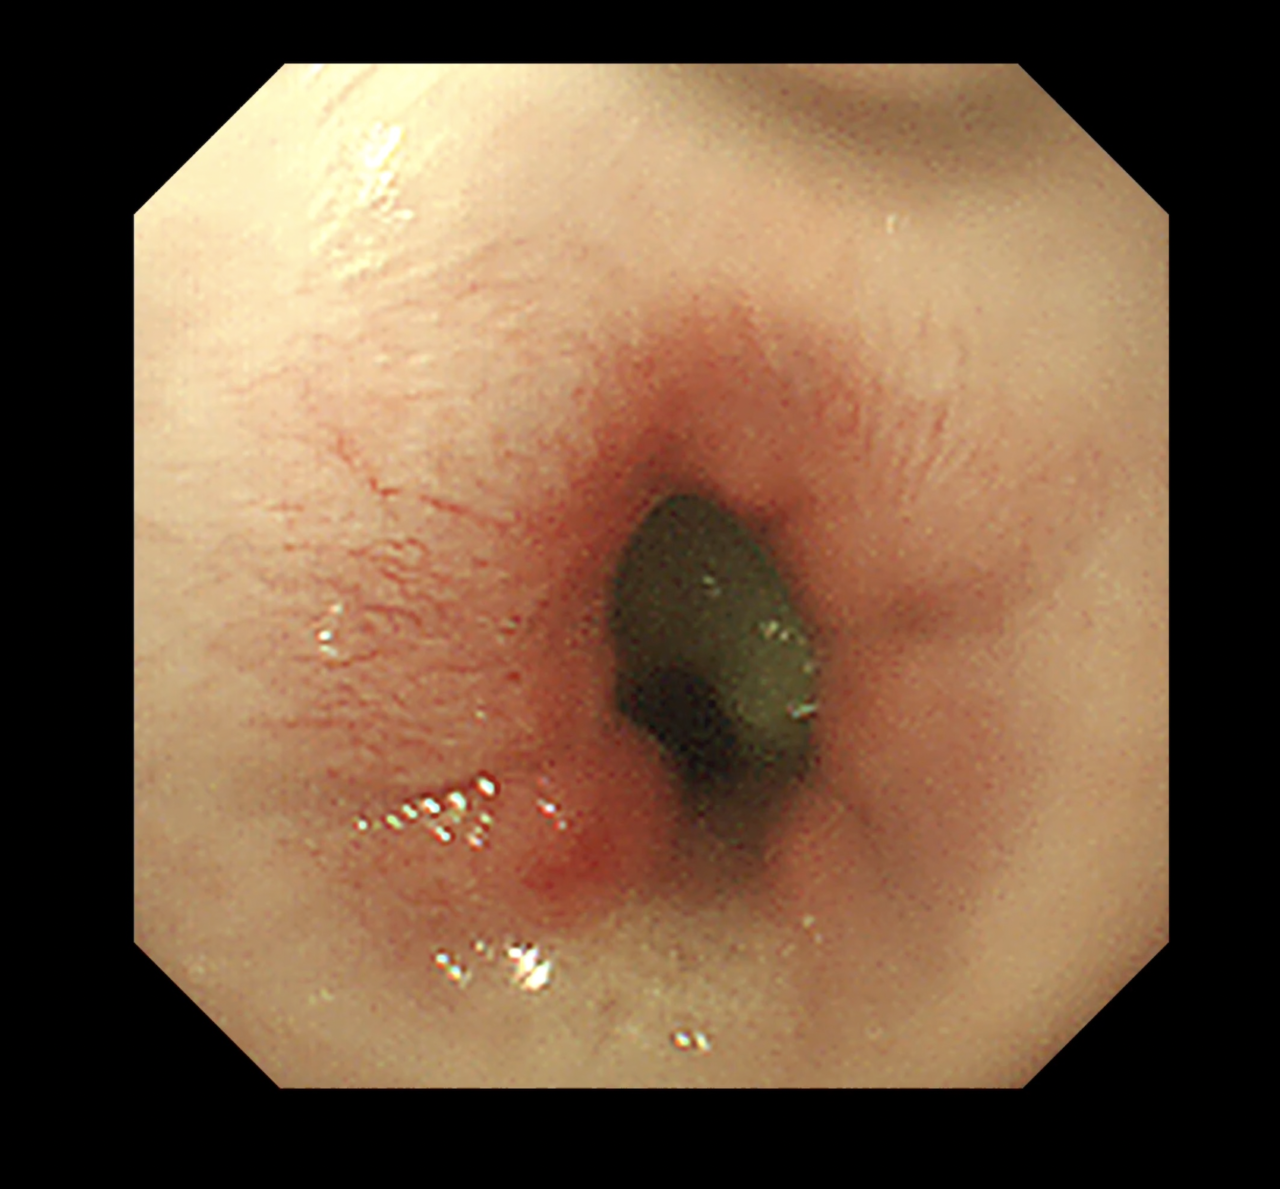

- 経過:摘出後は嘔吐や食欲不振もなく、順調に回復。軽度の炎症あり。

- 内視鏡処置の利点としては外科的な開腹手術等を回避でき、組織へのダメージがありません。